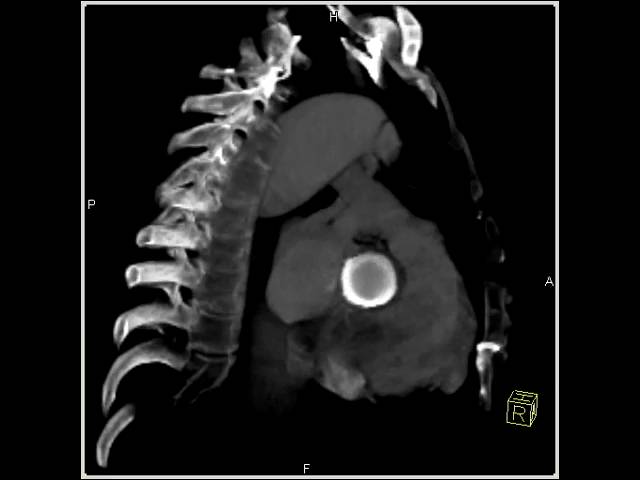

Операция Росса у мужчины 55 лет. SSFP-изображение в плоскости путей оттока из ЛЖ демонстрирует анастомоз и закрытый клапан легочного ствола в позиции аортального клапана (стрелки). Незначительный послеоперационный выпот в полость перикарда определяется как случайная находка (с разрешения B.Djavidani, UniversityofRegensburg).

Операция Росса у мужчины 55 лет. SSFP-изображение параллельно плоскости клапана демонстрирует закрытый клапан и тонкие створки клапана (стрелка) во время диастолы. Двусторонний выпот в плевральную полость определяется как случайная находка (с разрешения B.Djavidani, UniversityofRegensburg).